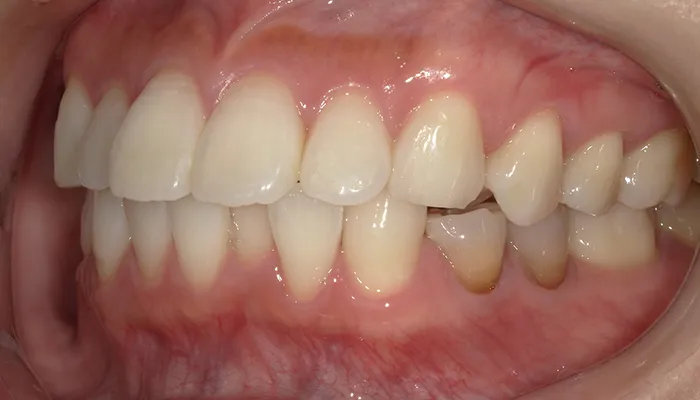

術前の口腔内写真

右下5番は大きく崩壊しており、保存不可能な状態でした。

また、下顎前歯部を中心に叢生があり、歯列が不均一でした。咬合関係が不安定で、清掃性も低下していました。

全体的に歯の色もやや黄みを帯びており、患者様からも審美的な改善希望が強くありました。